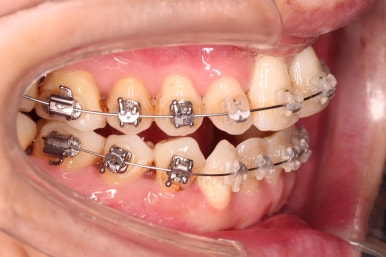

1. 초진 시 입안의 모습

부산구순구개열교정 키다리아저씨치과에 처음 내원하셨을 당시의 입안의 모습입니다.

이번 환자분도 이와 같은 일반적인 특징이 그대로 나타나 있었습니다.

양측성 구순구개열이었으므로 작은 앞니(대문니와 송곳니 사이)가 양쪽 다 결손이었고, 또 다른 이유로 아래 앞니도 1개 없는 상태였습니다.

위아래 장치를 부착했습니다.